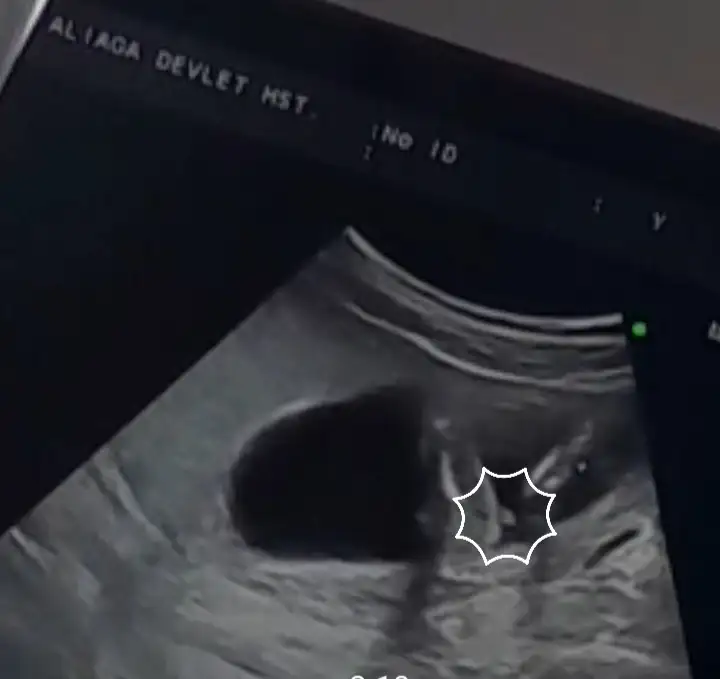

bende ctesi gittim ultrasona göre 11+5 olmuşuz belki hareketlerini görürüm dedim ama uyuyordu galiba ense kalınlığı 1.4 çıktı iyi dedi ondan sonra üç hafta sonra gel cinsiyete bakalım dediBizde bugün 11+4 olmuşuz regle göre 2 3 gün gerideydik yakalamışız çok şükürkalp atışı 168, ense burun vs iyi dedi doktorum cinsiyet yorumu yapmadı salı günü nipt cikacak umarım sağlıklıdır bebeğim yüz ustu yatıyordu ve uyuyordu çok bir şey anlamadım ben o yüzden bazı ilaçlara başladı folik asit elinde ki bitsin bırak dedi, 1 kilo vermişim bu aylarda vermenin çokta önemli olmadığını söyledi bilginiz olsun, sağlıklı hayırlı evlatlar imiz olsun inşallah

İkili tarama testi yaptırdınız mi orada mi soylediler ense kalınlığını yoksa rutin muayenede mi soyleniyorbende ctesi gittim ultrasona göre 11+5 olmuşuz belki hareketlerini görürüm dedim ama uyuyordu galiba ense kalınlığı 1.4 çıktı iyi dedi ondan sonra üç hafta sonra gel cinsiyete bakalım dedi

yok ikili test yaptırmadık kendi doktorumuz ölçümünde söylediİkili tarama testi yaptırdınız mi orada mi soylediler ense kalınlığını yoksa rutin muayenede mi soyleniyor